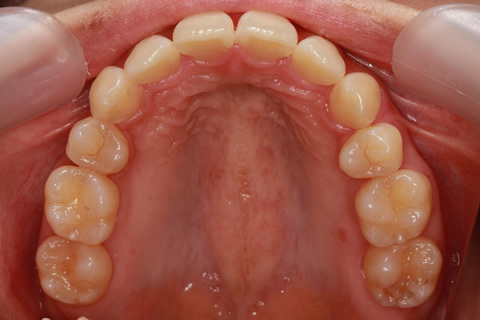

治療後